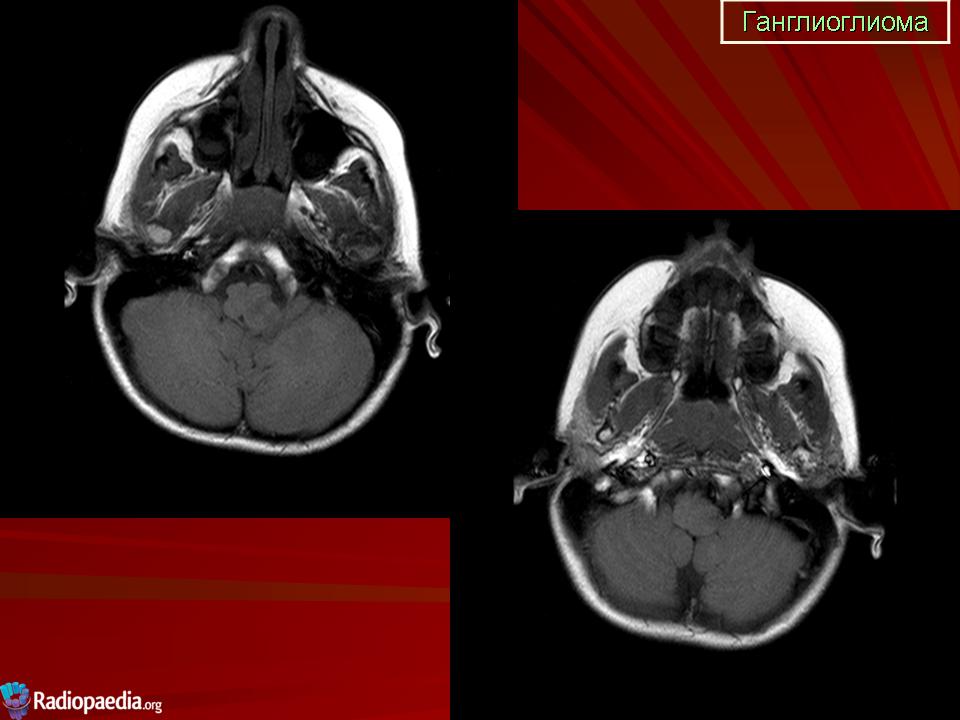

Ганглиоглиома — бифракционная опухоль, состоящая из элементов ганглиоцитомы и пилоцитарной астроцитомы. Локализуется преимущественно в полушариях головного мозга. Макроскопически представляет собой плотную четко отграниченную от ткани мозга опухоль, которая нередко содержит кисту.

Ганглиоглиома

Продолжение.